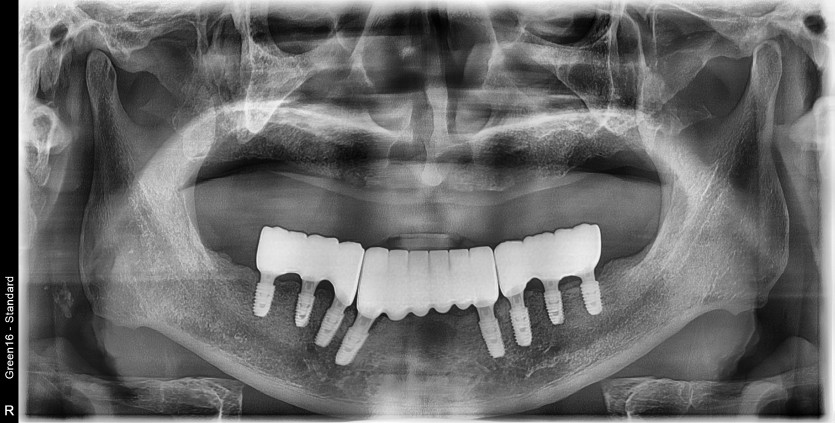

만 68세 하악 전체 임플란트 증례

하악 전체 임플란트 증례입니다.

6개의 임플란트로 완성하였습니다.